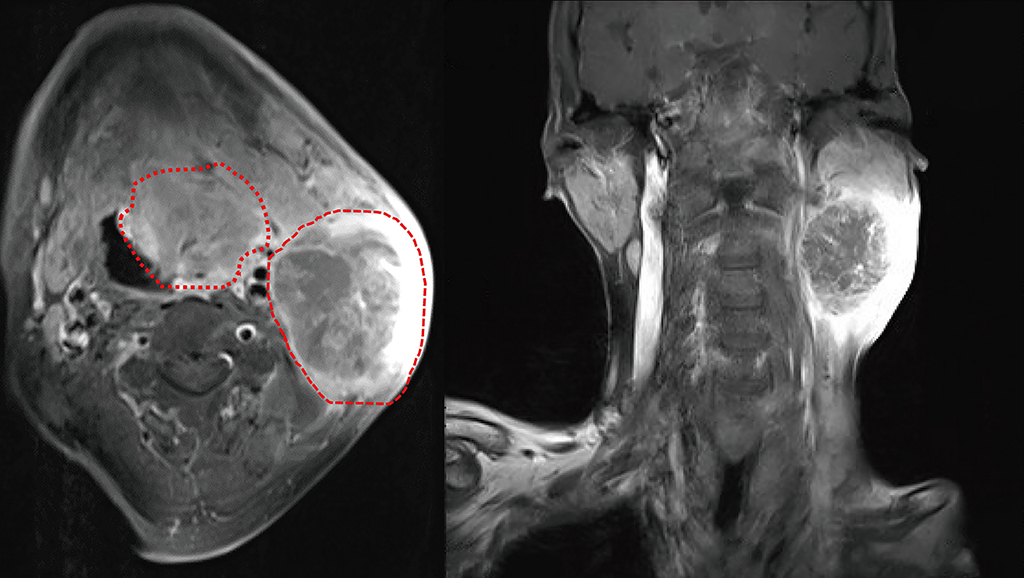

51歲男子因舌頭潰瘍,久而未痊癒。圖左為核磁共振顯示嚴重的腫瘤侵犯;圖右為癌症侵犯下巴骨頭及皮膚。

51歲新竹周姓男性,今年初開始有舌頭潰瘍,久未痊癒。但因擔心新冠肺炎的疫情,不敢到醫院或診所求診,舌頭潰瘍不停地擴大,又因為疫情期間,大多時間都戴著口罩,家人也沒發現他的異樣;直到今年八月,腫瘤吃穿皮膚及下巴骨頭,才由新竹某醫院切片後,慕名到彰基醫學中心找院長陳穆寬教授就診,才驚覺已經口腔癌第四期。

台灣耳鼻喉暨頭頸外科醫學會理事長,亦是彰基醫學中心院長陳穆寬教授當即為病人安排相關檢查(核磁共振、正子攝影、胃鏡、肝膽超音波),並以最快的時間安排病人入院進行手術治療。但是在入院前新冠肺炎PCR採撿,竟意外發現病人呈陽性反應,依據相關規定,必須進行隔離七天後才能再入院安排手術。幸而手術團隊在病人解除隔離後,立即安排病人入院進行手術,切除全部舌頭和下巴,以及雙側頸部淋巴廓清手術,並同時施行顯微皮瓣重建手術,不讓病人再次延遲治療。陳穆寬院長感慨的表示 :「 這是上帝給我們的考驗。」感染新冠肺炎後的致死率,在青壯年病人身上大約萬分之五左右,但因為害怕疫情而延誤就醫、延遲手術時間,卻是讓這些口腔癌的病人死亡率增加許多。